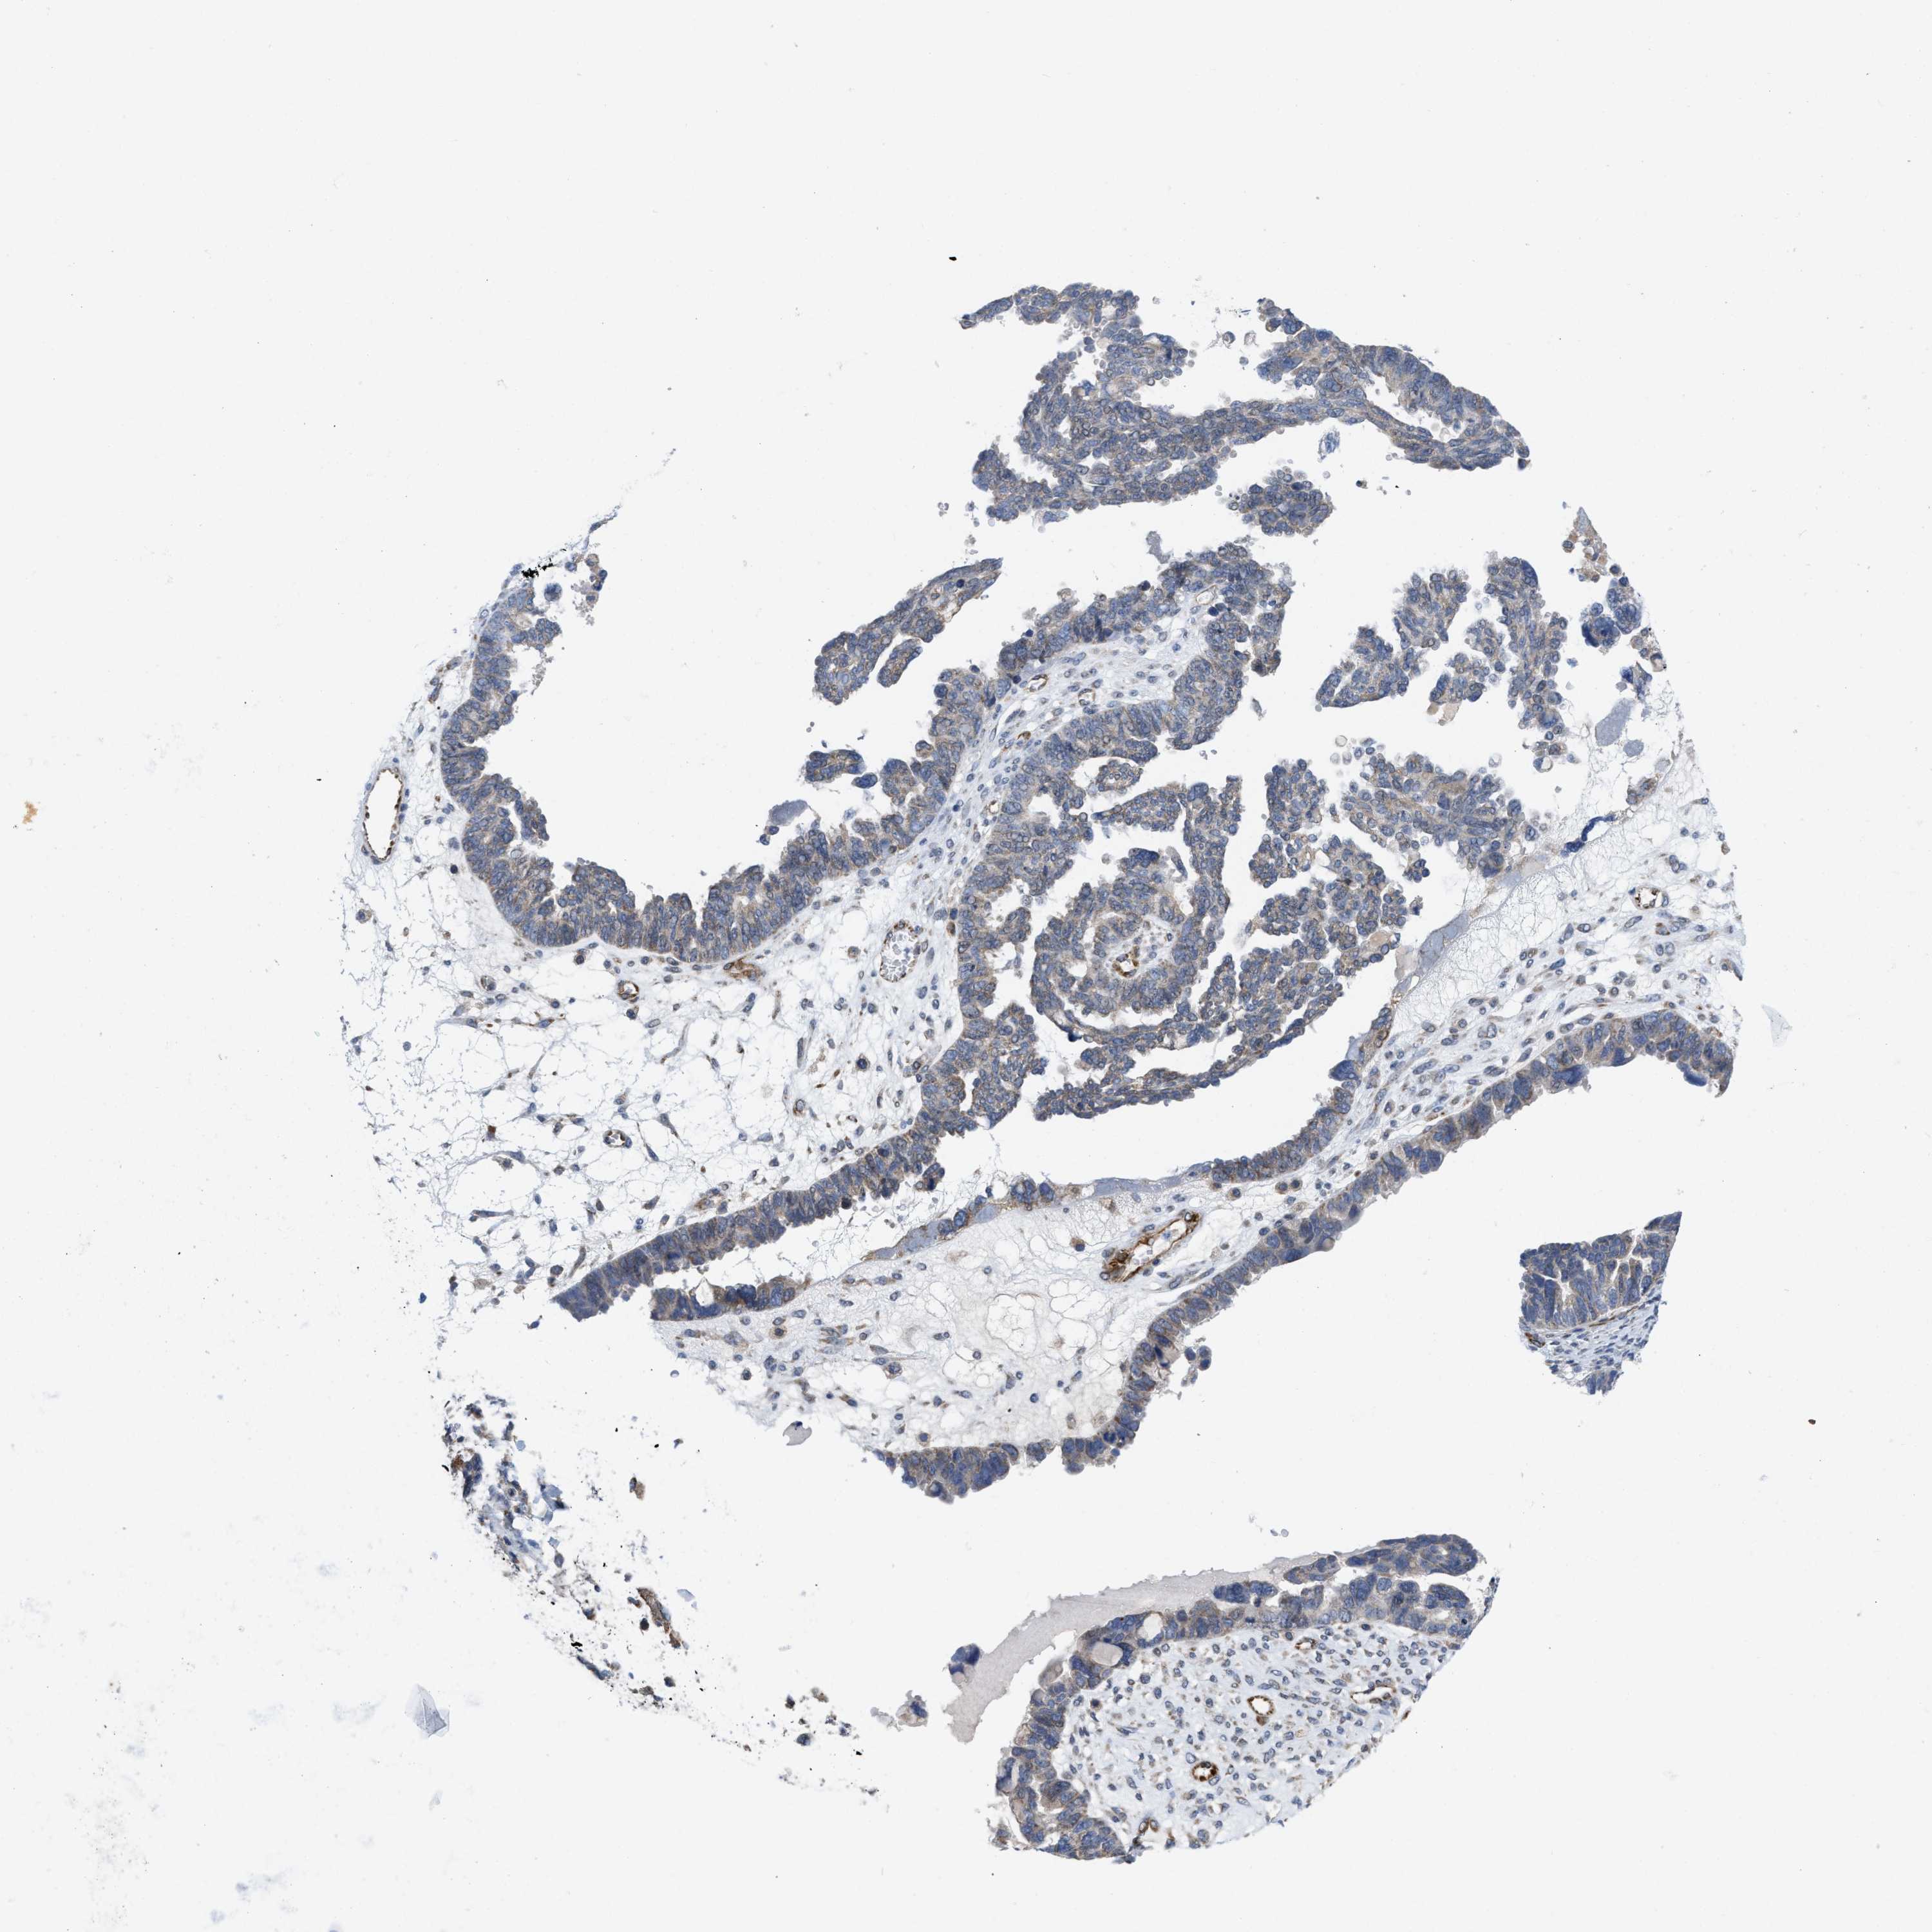

OVARIAN CANCER - Protein expressioni

A mouse-over function shows sample information and annotation data. Click on an image to view it in a full screen mode. Samples can be filtered based on level of antibody staining by selecting one or several of the following categories: high, medium, low and not detected. The assay and annotation is described here.

Note that samples used for immunohistochemistry by the Human Protein Atlas do not correspond to samples in the TCGA dataset.

Antibody stainingi

Antibody staining in the annotated cell types in the current human tissue is reported as not detected, low, medium, or high, based on conventional immunohistochemistry profiling in selected tissues. This score is based on the combination of the staining intensity and fraction of stained cells.

Each image is clickable and will lead to virtual microscopy that enables deeper exploration of all samples and also displays staining intensity scores, fraction scores and subcellular localization as well as patient and tissue information for each sample.

Antibody HPA019460

Staining

High

Medium

Low

Not detected

Intensity

Strong

Moderate

Weak

Negative

Quantity

>75%

75%-25%

<25%

None

Location

Nuclear

Cytoplasmic/membranous

Cytoplasmic/membranous,nuclear

Cystadenocarcinoma, serous, NOS

Carcinoma, endometroid

Cystadenocarcinoma, mucinous, NOS

Carcinoma, NOS